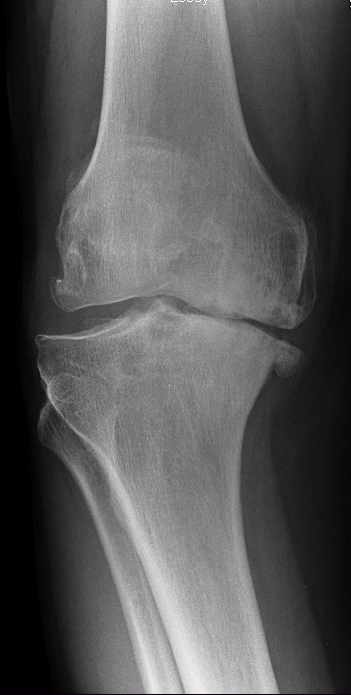

Osteoarthritis of the knee, also known as knee OA, is a degenerative joint disease that primarily affects the articular cartilage and surrounding structures in the knee joint. It is the most common form of arthritis and a leading cause of chronic pain and disability among older adults. Knee OA typically develops slowly over time due to the wear and tear on the joint, but it can also occur as a result of previous knee injuries or conditions that affect joint alignment.

In knee OA, the protective cartilage that covers the ends of the bones within the knee joint gradually deteriorates, leading to friction, inflammation, and damage to the underlying bone. This results in pain, stiffness, swelling, and reduced range of motion in the affected knee. As the disease progresses, bone spurs (osteophytes) may develop, further contributing to joint pain and dysfunction.

Knee OA is more common in individuals over the age of 50, although it can affect people of all ages. Certain risk factors increase the likelihood of developing knee OA, including obesity, previous knee injuries, repetitive stress on the knee joint, genetic factors, and conditions such as rheumatoid arthritis or gout.

The diagnosis of knee OA is typically based on a combination of clinical evaluation, medical history, physical examination findings, and imaging studies such as X-rays or MRI scans.